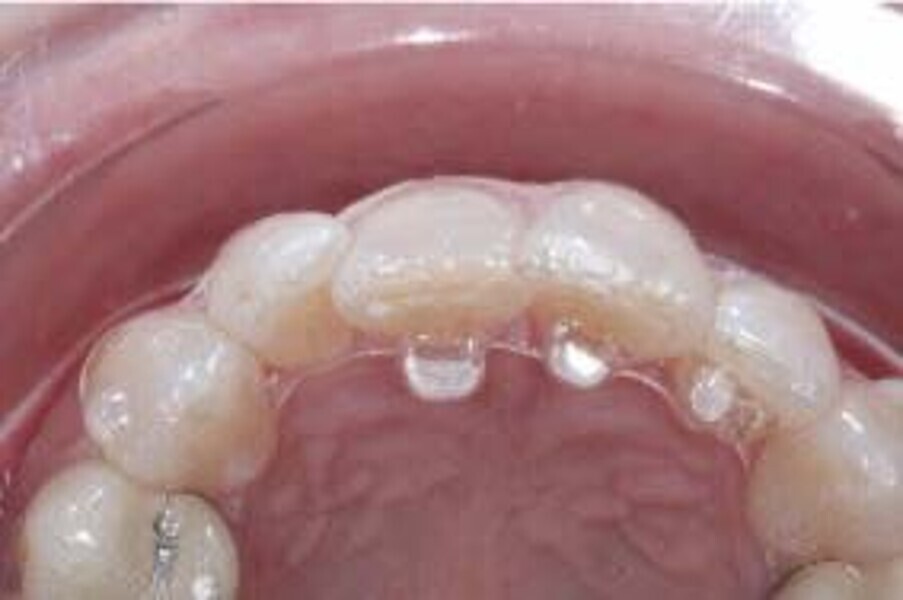

En raison de l’âge du patient, les aligneurs ont été changés tous les dix jours, dans le cadre d’un traitement d’une durée inférieure à six mois. À la fin de la première série d’aligneurs, un nouveau plan de traitement numérique comportant cinq autres aligneurs a été conçu, en vue d’améliorer l’intercuspidation des molaires sans élastiques. (Photos : Dr Alessandro Greco)

Le plan de traitement numérique (ClinCheck) avait prévu douze aligneurs pour l’arcade maxillaire et dix-sept pour l’arcade mandibulaire. Les objectifs du traitement visaient à combiner les mouvements verticaux d’extrusion des dents postérieures et les mouvements d’intrusion des dents antérieurs, au moyen de rampes d’occlusion, tout en utilisant des taquets d’extrusion pour assurer la désocclusion des dents postérieures et l’intrusion des dents antérieures inférieures, nécessaires au nivellement de l’arcade mandibulaire. La courbe de Spee a été nivelée et le profil plat ainsi que la position des lèvres ont été améliorés par une vestibulo-version des incisives supérieures et inférieures. Le plan avait prévu des élastiques de classe II pour faciliter la vestibulo-version des dents inférieures et les puissants contacts occlusaux postérieurs, avec une extrusion relative des dents postérieures. Une morphologie plus large de l’arcade et une intercuspidation idéale ont été obtenues par des mouvements de torque proches de 0° des dents latérales et postérieures supérieures. Aucune conception technique excessive n’avait été prévue dans le plan de traitement numérique. En raison de l’âge du patient, les aligneurs ont été changés tous les dix jours, dans le cadre d’un traitement d’une durée inférieure à six mois. À la fin de la première série d’aligneurs (Figs. 20–24), un nouveau plan de traitement numérique comportant cinq autres aligneurs a été conçu, en vue d’améliorer l’intercuspidation des molaires sans élastiques. La durée totale du traitement a donc été prolongée jusqu’à 7,5 mois puisque les aligneurs supplémentaires étaient changés toutes les semaines.

Lors du suivi à un an, alors que le patient portait un appareil de rétention (appareil de rétention Vivera avec rampes d’occlusion, Align Technology), le résultat était stable et l’intercuspation était nettement meilleure (Figs. 38–42).